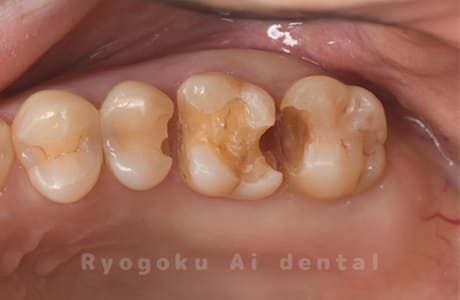

Case08

-

- 原因

- 虫歯

- 治療内容

- セラミックインレー

- 治療費用

- 77,000円

奥歯の黒い点が気になるということで来院された患者さんです。白い詰め物を外したところ、虫歯が中で大きく広がっていたため、患者さんと相談し、セラミックインレーで治療を行いました。

<リスク・副作用>

過度の咬合や衝撃で割れることがあります。